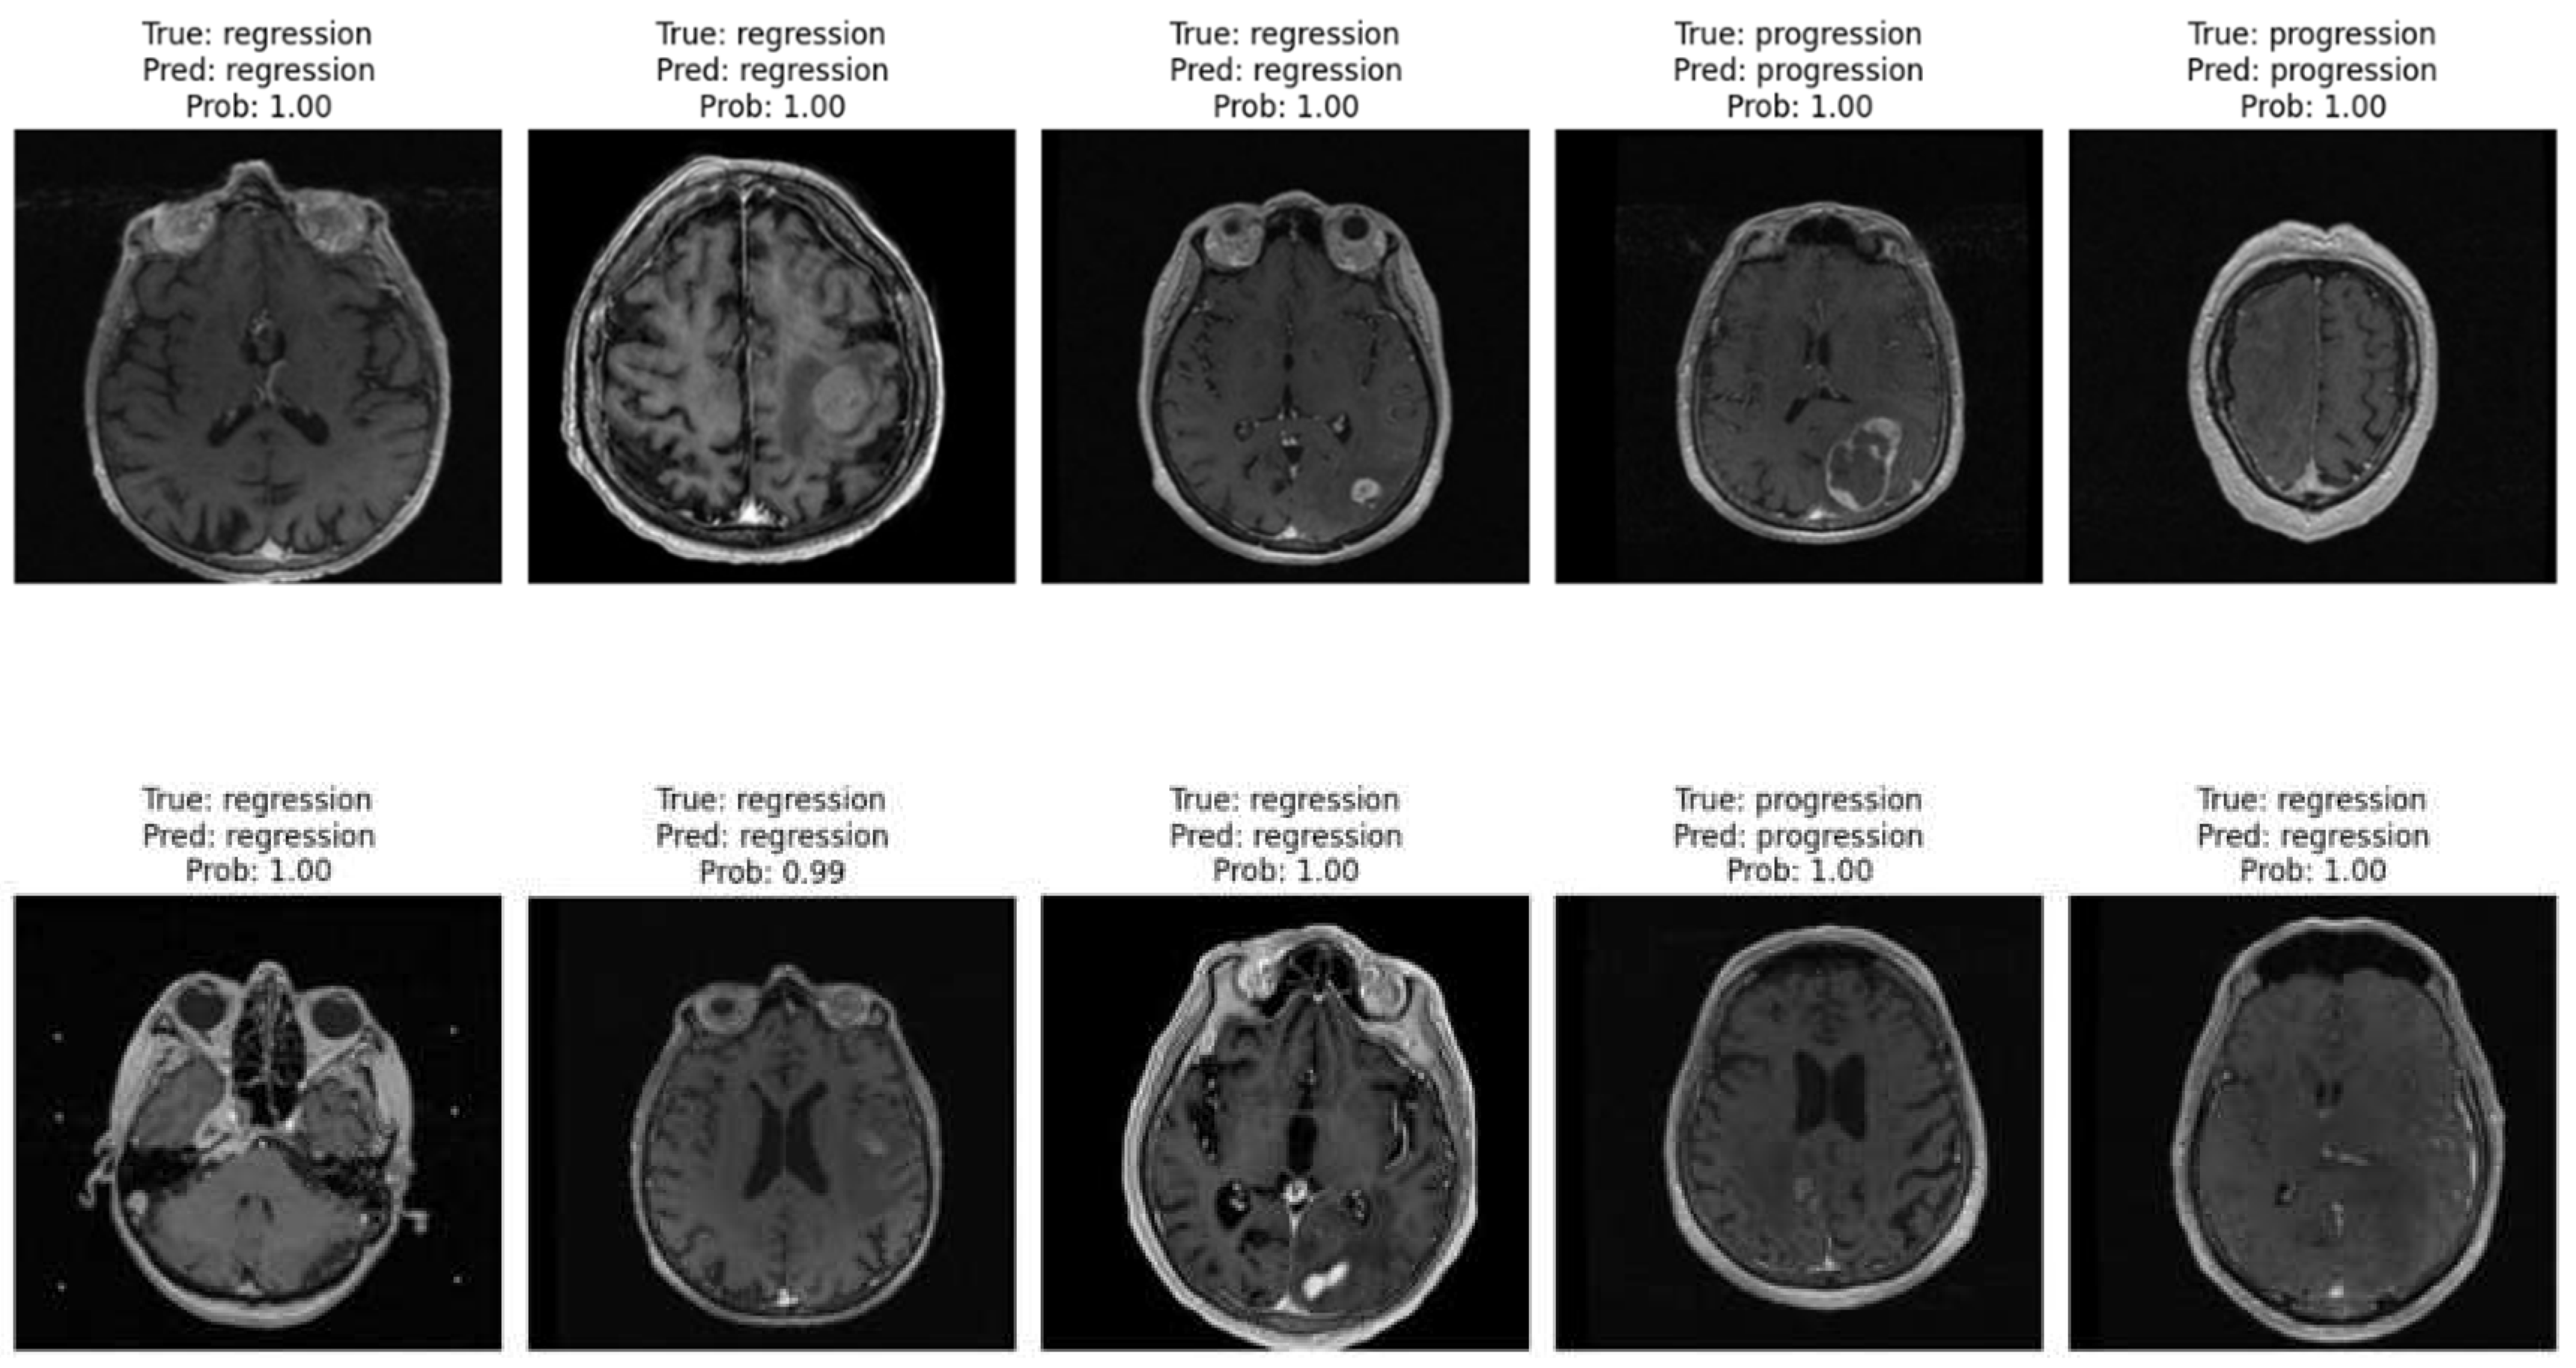

The brain_met_1 Image Dataset was stored in cloud on Google Drive, consisting of two subfolders: progression and regression. For training, the train_ds is used and for validation, the valid_ds is used. The Image Dataset contains 3194 MRI brain metastasis images, with 2320 images of regression class '1' and 874 images of progression class '0'. See example of images from the dataset in Figure 1.

Figure 1. Example of images from the dataset.